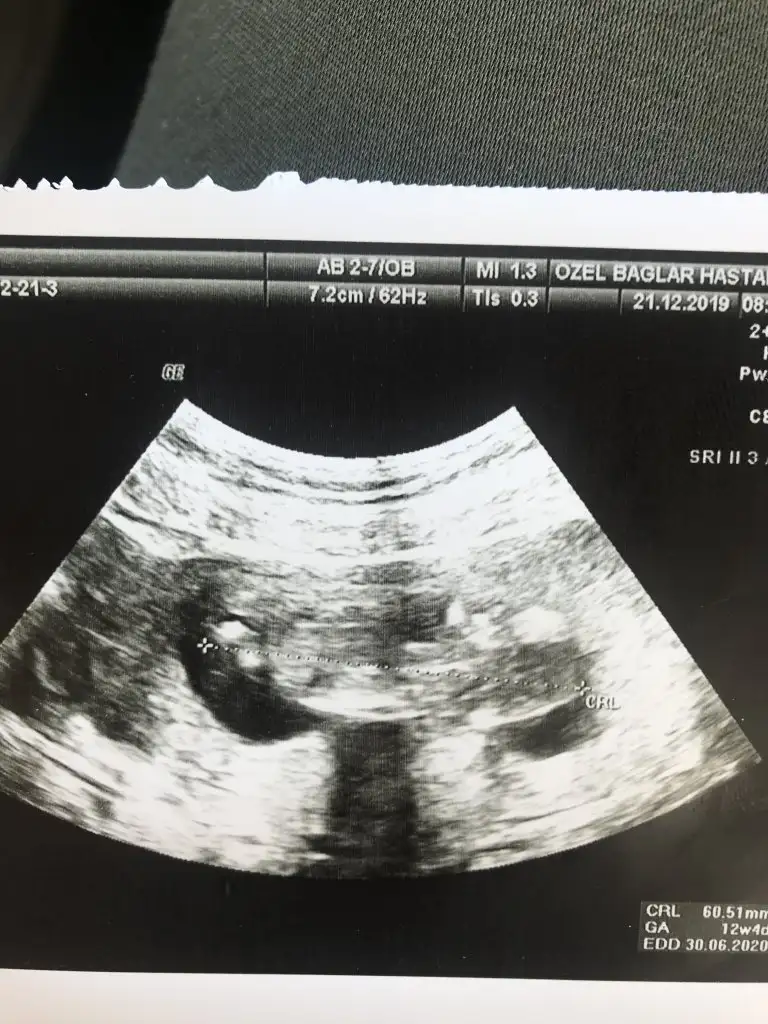

Maalesef elimde ayrı günlerde çekilmiş iki usg tek var cuma günü gideceğim doktora bakalım okursa onu paylaşırım.Başka usg varmı 11 yada 12 hafta kız gibi ama emin olamıyorum

Net degil usg gördügüm nub ise erkek gibi başka varsa usg 11 yada 12 hafta paylaşın bu usg kaç haftalıkbanada tahminde bulunurmusunuz rica etsem

Erkektir o zamanbu usg 12 +3 haftalık doktor %90 erkek dedi bu perşembe netleşecek